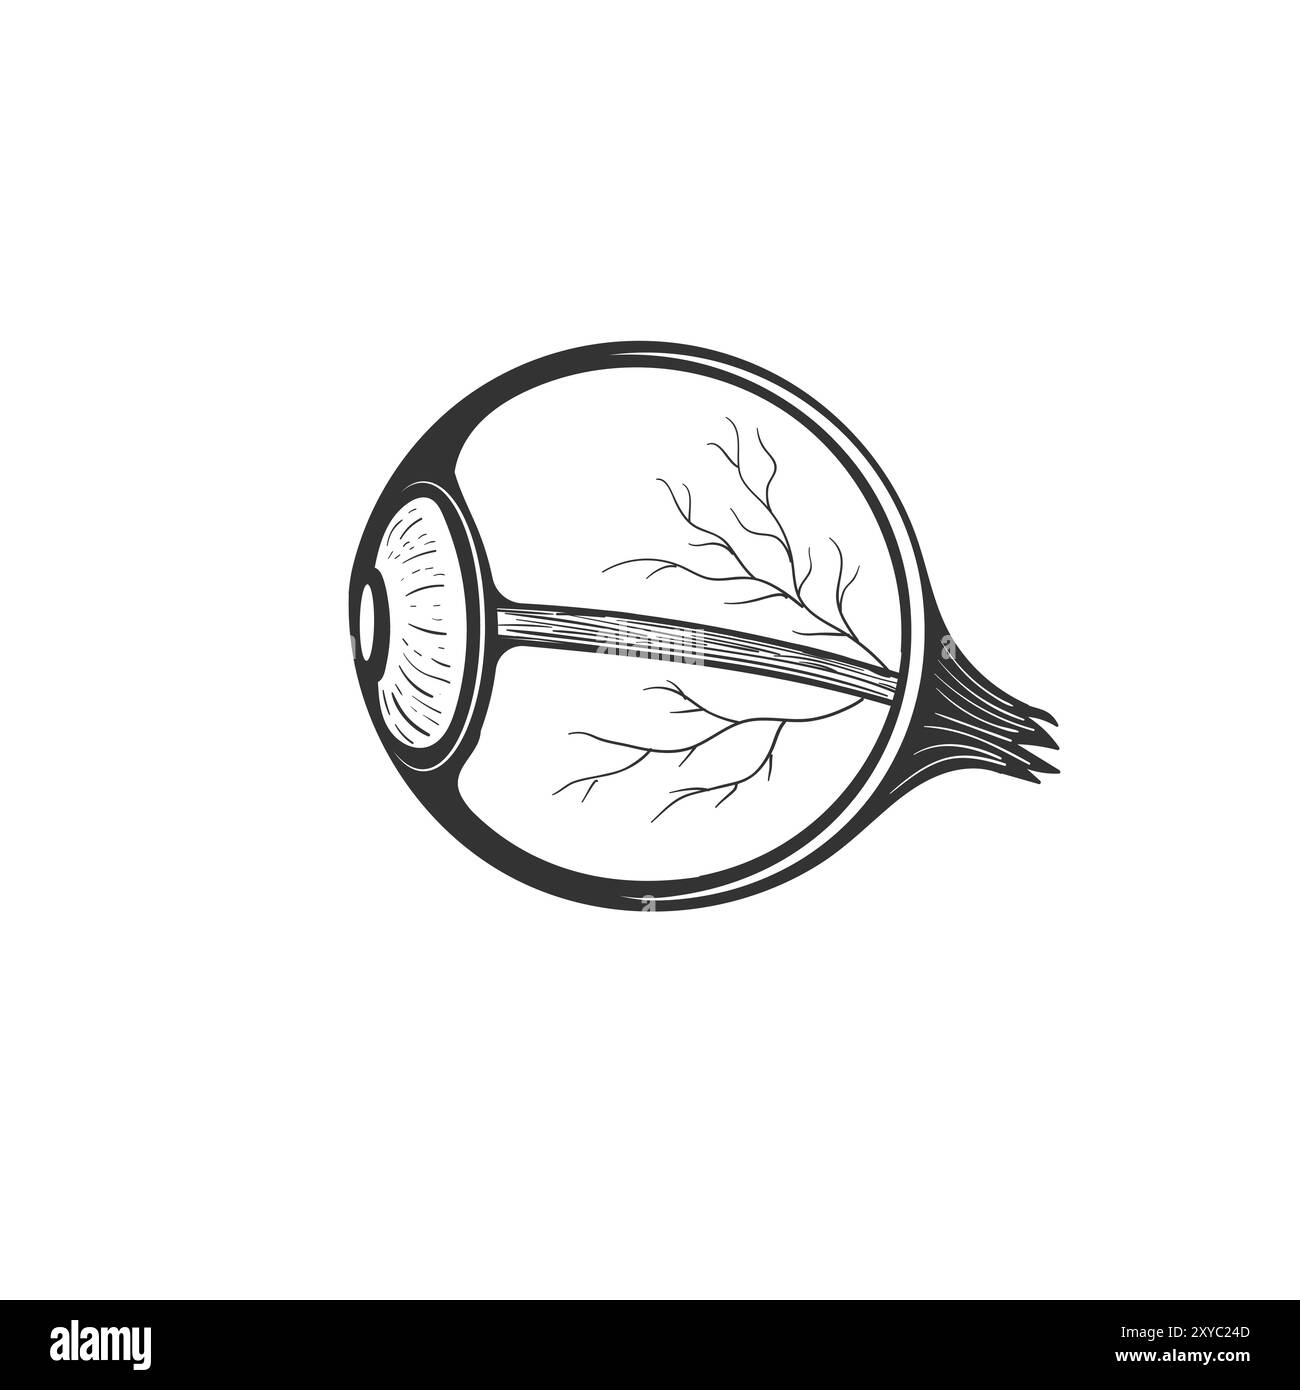

Isolated Cross Section of the Human Eyeball for Medical Education. Vector Illustration Stock Vectorhttps://www.alamy.com/image-license-details/?v=1https://www.alamy.com/isolated-cross-section-of-the-human-eyeball-for-medical-education-vector-illustration-image619223709.htmlRF2XYC24D–Isolated Cross Section of the Human Eyeball for Medical Education. Vector Illustration

RF2S6CPD2–Human eyeball structure, eye anatomy cross section, medicine and biology, isolated linear icon. Ophthalmological clinic, ophthalmology and healthcare. Sight or vision medical correction outline symbol. Eye anatomy and human eyeball structure isolated line icon